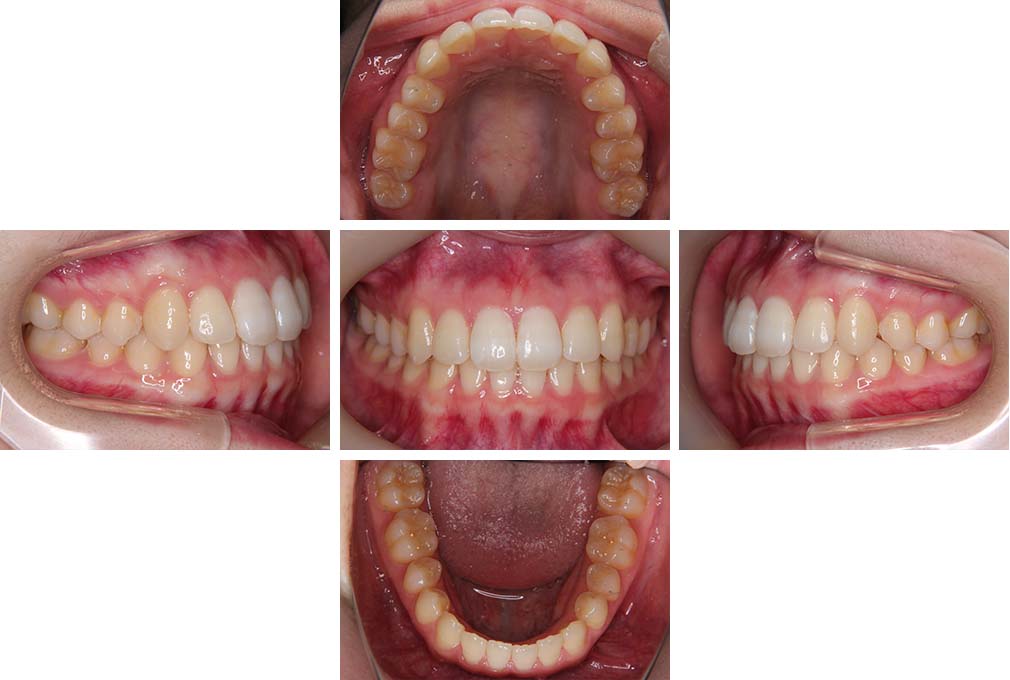

CASE:02

下顎前歯部叢生、小臼歯4歯先天欠損

初診時年齢 14歳3か月

性別 女性

治療費の目安 70万円(治療開始時)

上顎左右側小臼歯3歯、下顎左側第二小臼歯の先天欠損と下顎前歯の叢生を主訴として近隣一般歯科から紹介来院した。

上顎左側第一、第二小臼歯、右側第一小臼歯、下顎左側第二小臼歯が先天欠損であったが、左上第二乳臼歯の根の吸収がほぼ無いことから、これを残すこととして、下顎左側乳臼歯と、右側第二小臼歯を抜歯していただきマルチブラケット装置を使用して動的治療を行った。矯正用ゴムなどの協力状態も良く2年0カ月(調整来院19回)で装置を撤去し保定へ移行した。動的治療終了13年2カ月での来院時には下顎左右側智歯が萌出していたが、垂直的に萌出していたため抜歯は行っていない。

治療前

14歳3か月

治療後

動的治療期間2年0カ月

16歳7か月

13年経過

動的治療終了後13年2カ月

30歳0か月